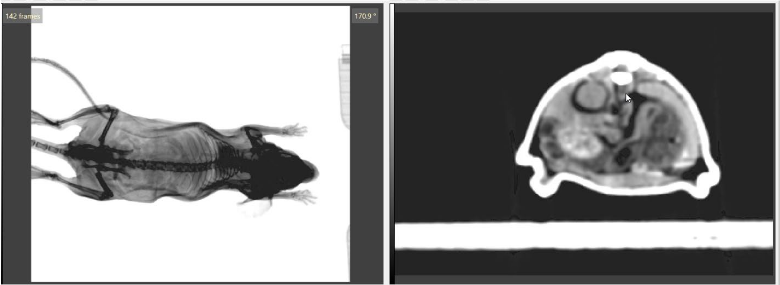

Fig 1. (left) 2D images of a plastinated mouse being acquired on the SmART+ system. (right) the respective reconstructed 3D CBCT image.